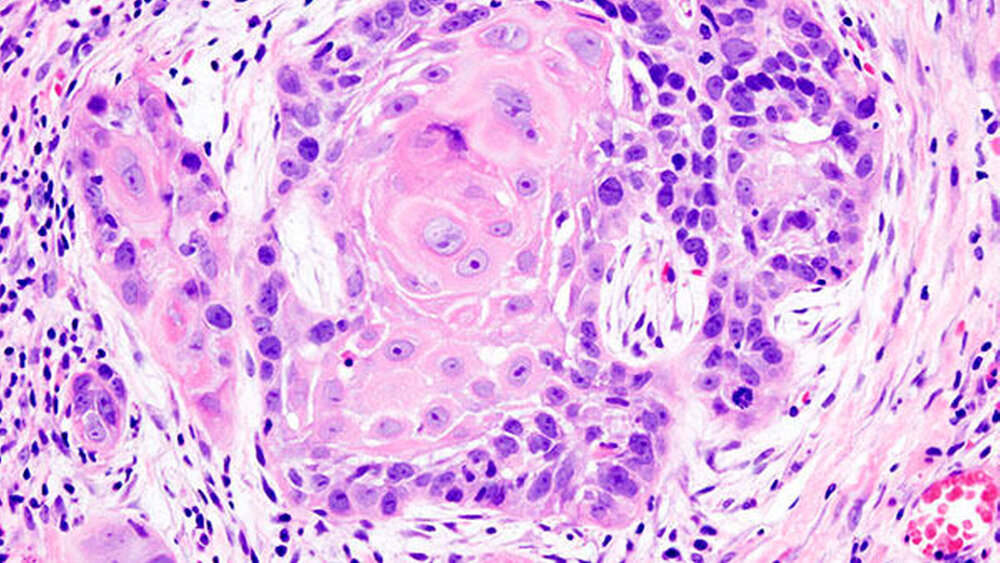

Es habe sich gezeigt, dass der Befund des Sentinellymphknotens signifikanten Einfluss auf das Gesamtüberleben nach drei Jahre hatte, bewerteten die Autoren die Ergebnisse. Es sei deshalb sinnvoll, die nur mit einem geringen Risiko für Komplikationen verbundene Biopsie des Sentinellymphknotens bei Patienten mit einem Plattenepithelkarzinom der Mundhöhle im Frühstadium durchzuführen. Dann könnten gegebenenfalls notwendige Therapieschritte eingeleitet werden, um die Heilungschancen der Patienten zu verbessern.